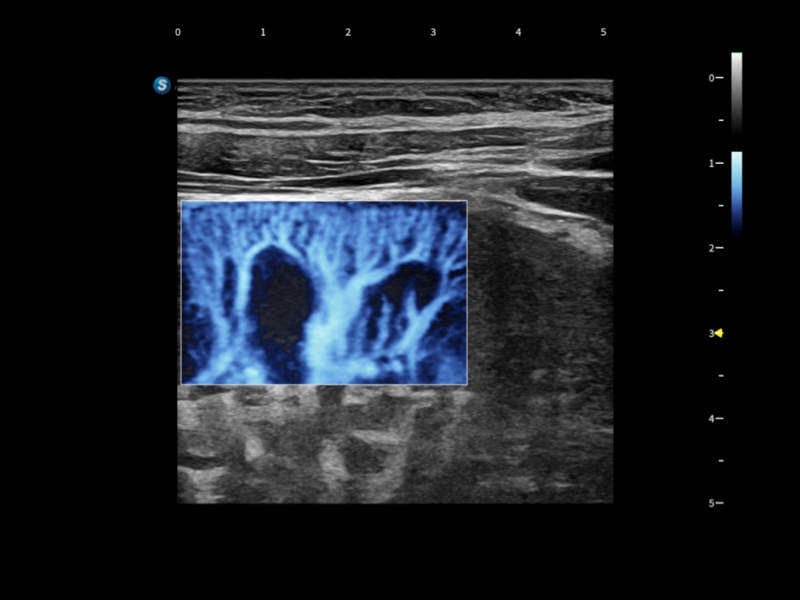

丰富的血流动力学检测技术,可在不同医疗场景中高效捕捉血流信号,助力临床诊疗。

在传统血流的基础上优化扫查和算法策略,能够更好的抑制组织信息,提炼红细胞运动信息,得到更高帧频,高灵敏度和分辨率的血流信号,还原更真实的血流动力学。

通过光照模型,使二维血流显示出立体的效果,增加血流的敏感性、成束性,减少外溢。可以和其他不同的血流技术联合使用,融合不同技术的优势。轻松应对微小血管,增强血流的立体效果,提升视觉敏感性。

通过创新的Matrix E自适应滤波算法,能有效滤除软组织和噪声信号,最大限度保留超低速微细血流的信号;结合超长时间域算法,极大提升细微血流的敏感性和空间分辨率,更真实的反应组织、包块的血流灌注情况。